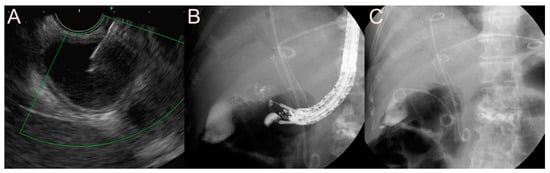

2.2. Stent for EUS-Guided Bile Duct (BD) Drainage

2.2.2. Use of the SEMS